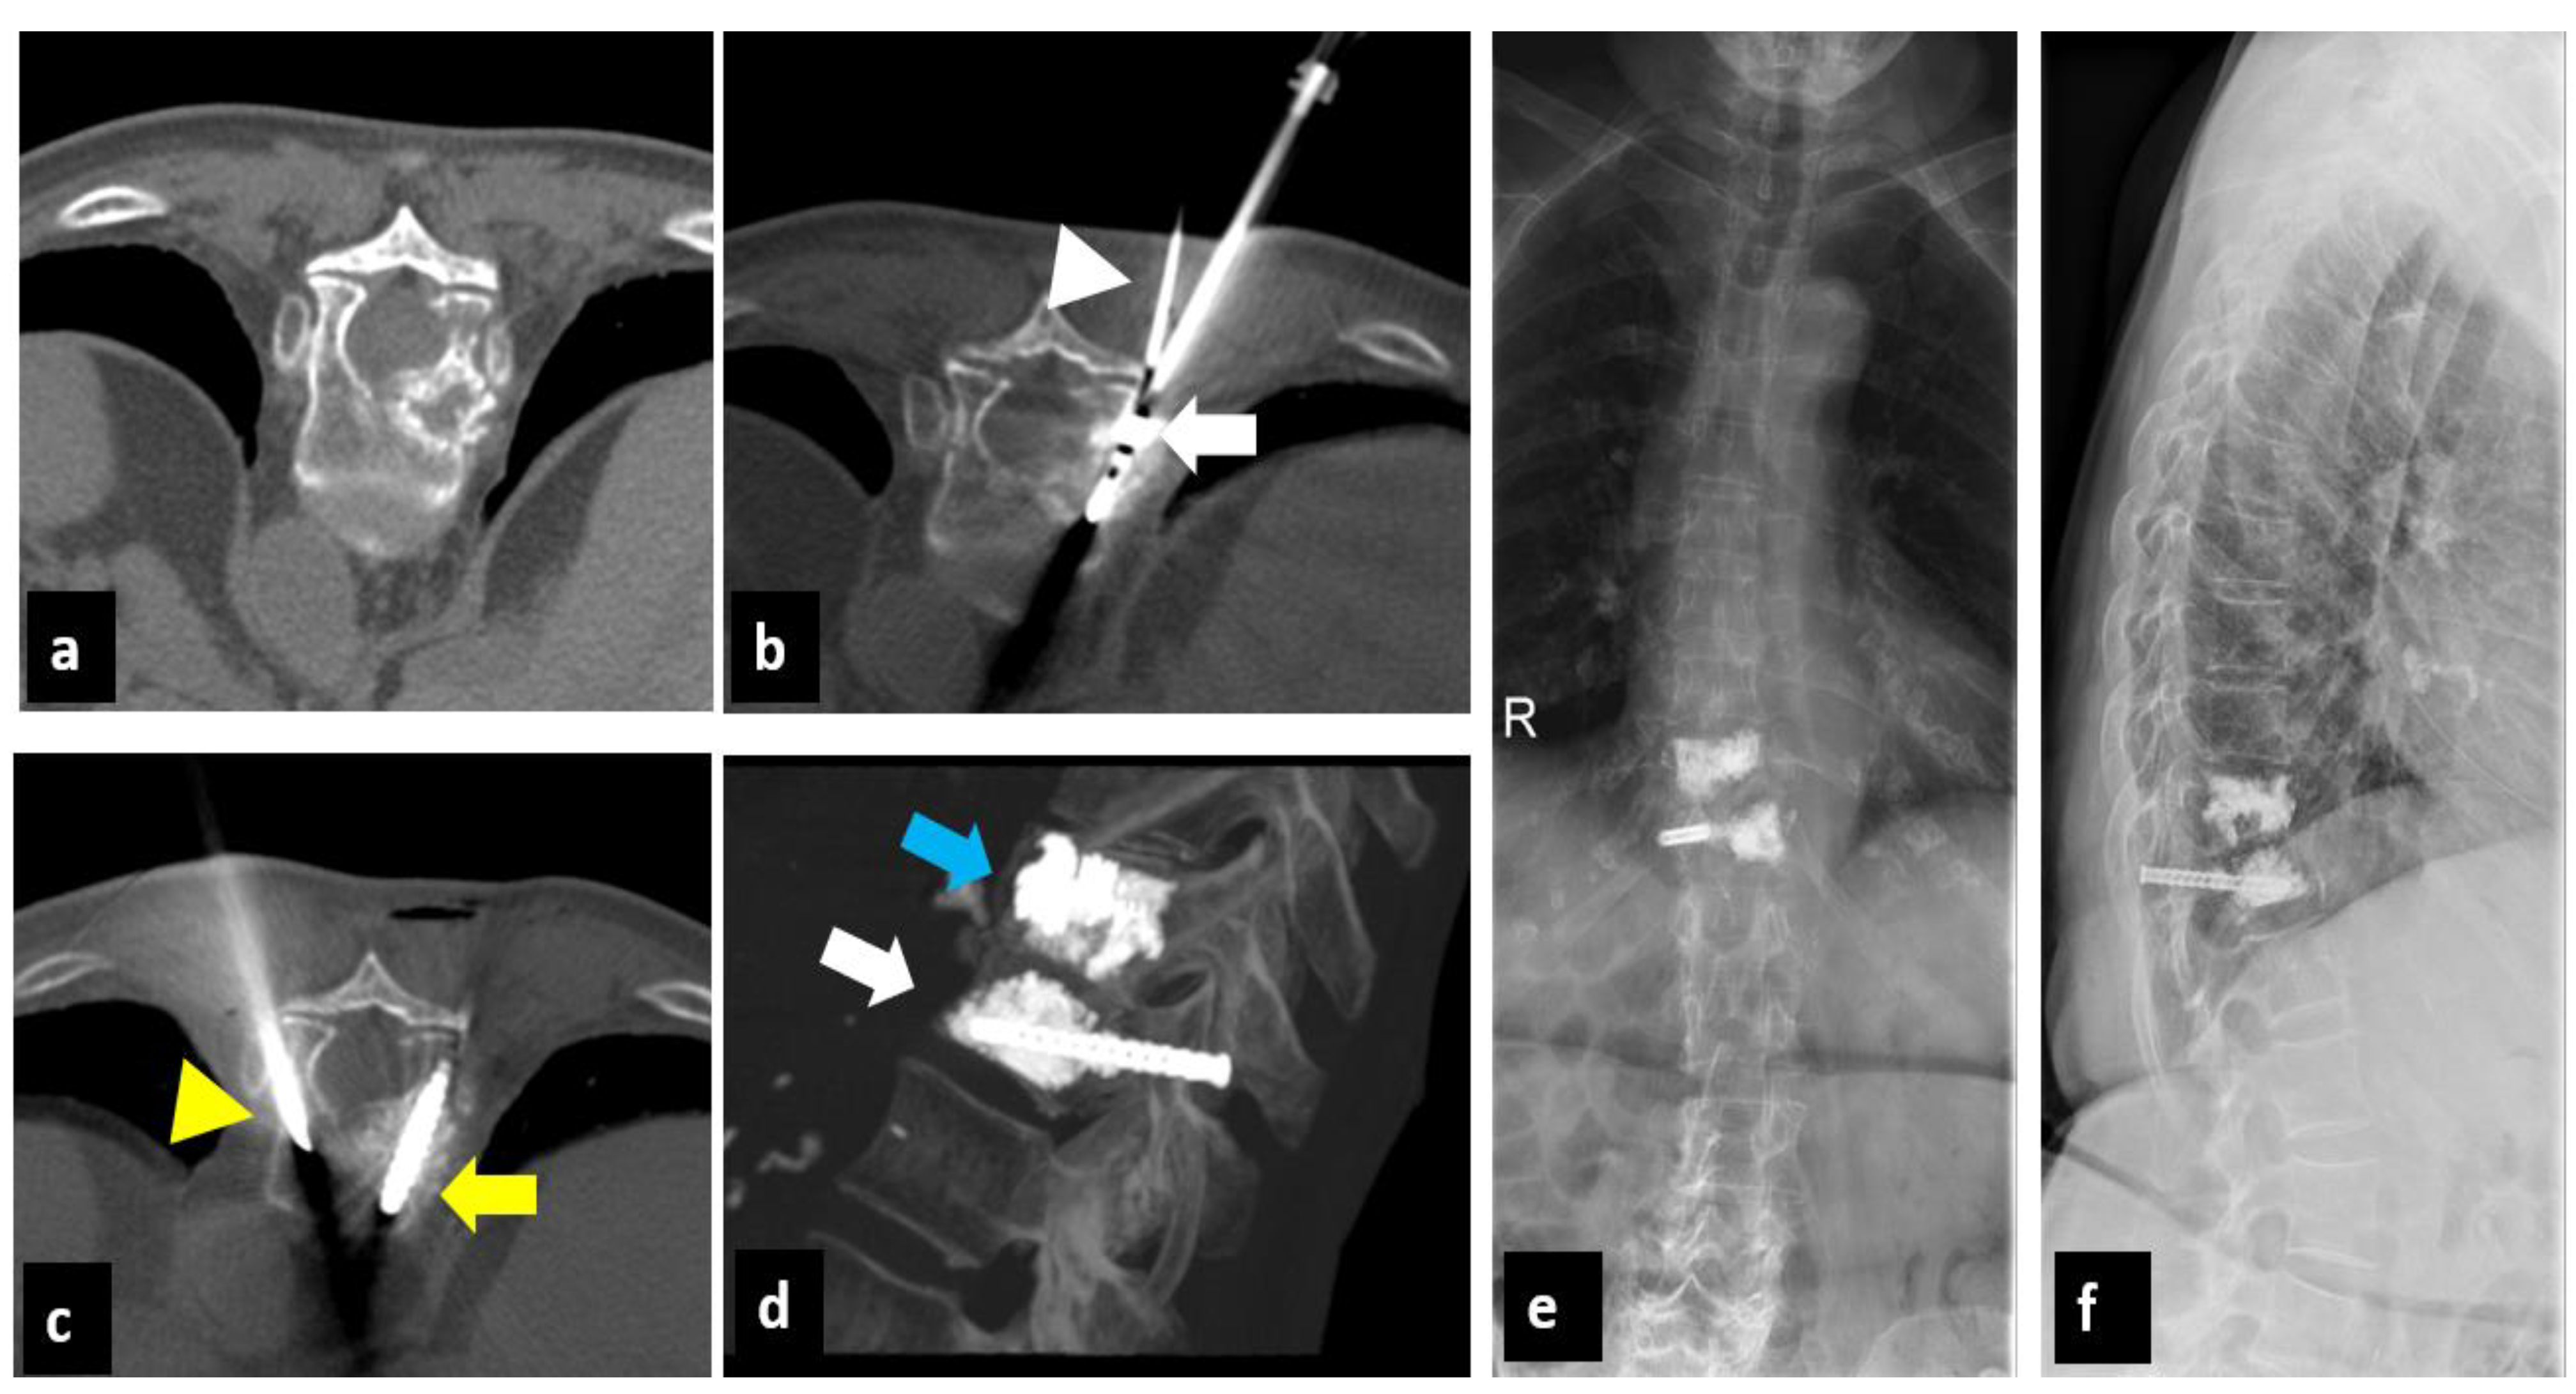

Percutaneous CT-Guided Microwave Ablation Combined with Pedicle Screw Fixation Followed by Vertebroplasty (MASFVA): Initial Experience of a Minimally Invasive Treatment of Vertebral Metastases with Extension to the Vertebral Pedicle

2.1. Treatment Technique